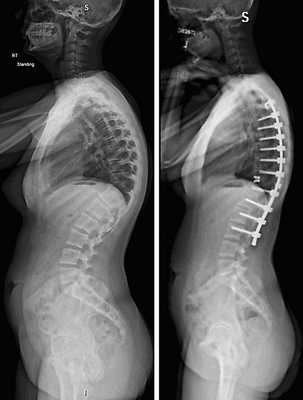

Коррекция кифоза грудного отдела.

| Транспедикулярная инструментация кифоза | 120000-165000 |

- Система создана для универсальной фиксации торакального и люмбального отделов позвоночника. Представляет собой «умную» комбинацию из титановых стержней и винтов, способствующих быстрому и качественному формированию артродеза.

Показаниями к вживлению ригидных конструкций транспедикулярной фиксации, в том числе и Krypton®, служат практически все случаи позвоночной нестабильности:

- выраженный листез позвонков;

- травмы позвоночника (вывихи, переломы и пр.);

- спинальные новообразования;

- дегенеративные патологии, сопровождающиеся неврологическим дефицитом, например, межпозвоночные поясничные грыжи; и кифоз;